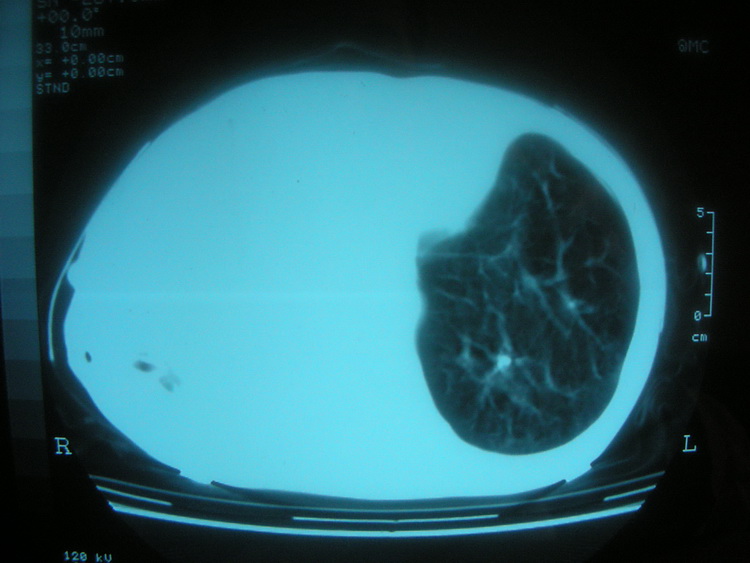

以下是引用卜一在2008-2-16 6:10:00的发言:[br]右肾增大,实质内明显见占位性病灶,并突出体外,密度不均匀。另双肺上叶见散在的斑片 索条及点状结节样致密影,右下肺门区不规则团块,右侧胸腔积液并形成局限性气胸。考虑:1 右肾癌。2 右肺门淋巴结转移及肺内 胸膜转移。3 右上肺陈旧结核。